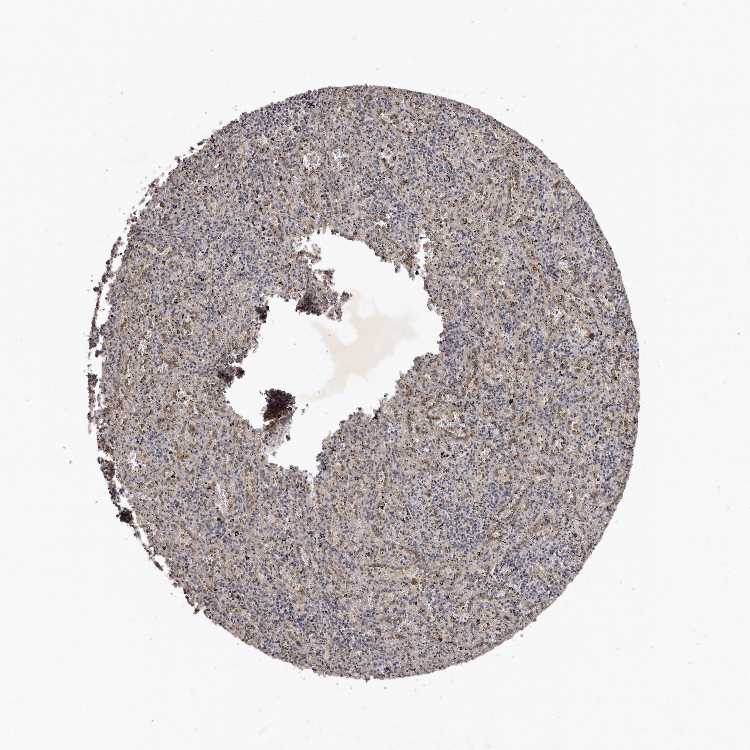

TISSUE PRIMARY DATA SPLEEN Show tissue menu

SPLEEN - Antibody stainingi

Antibody staining in the annotated cell types in the current human tissue is reported as not detected, low, medium, or high, based on conventional immunohistochemistry profiling in selected tissues. This score is based on the combination of the staining intensity and fraction of stained cells.

Each image is clickable and will lead to virtual microscopy that enables deeper exploration of all samples and also displays staining intensity scores, fraction scores and subcellular localization as well as patient and tissue information for each sample.

Antibody HPA027895

Cells in red pulp Low

Cells in white pulp Not detected